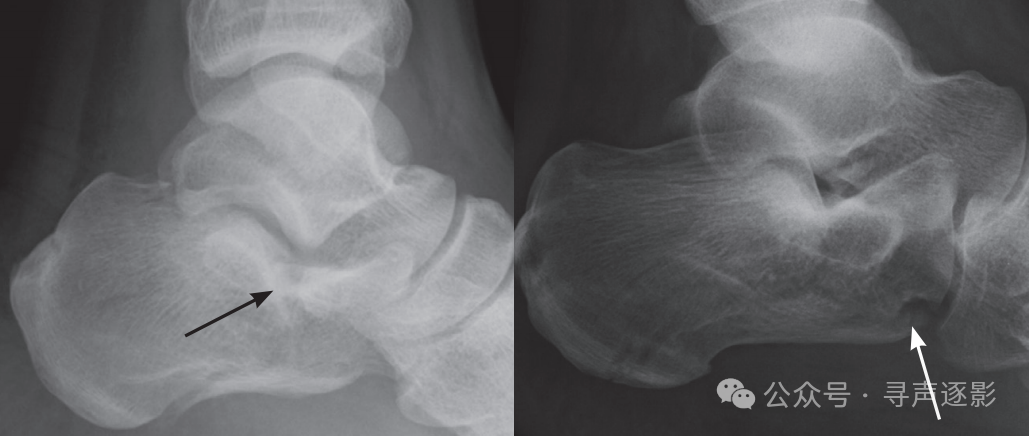

关节内骨折(箭头所示)累及距下关节(左图)或跟骰关节(右图)。

Bohler 角变平是侧位 X 线片所示跟骨骨折的主要征象。

跟骨体内若出现一条硬化线或密度增高影(箭头所指),可能就是嵌插骨折的**征象。这是一种经跟骨结节部的关节外骨折,通常发生在足跟部相对轻微的跌落后。